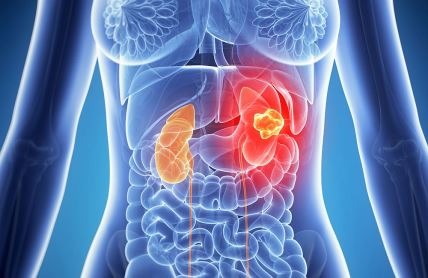

Hronična bolest bubrega se često razvija tiho: Evo koje analize su važne